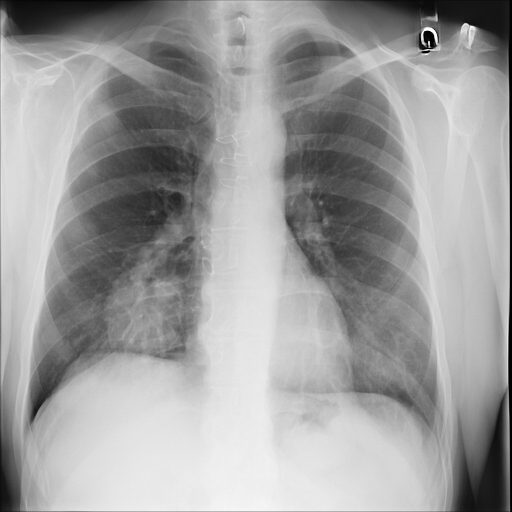

In Fig. 1, we show four ϵitalic-ϵ\epsilon-LDP-processed CXR images of clinical cases obtained with the image domain LDP, which directly imposes the Laplace mechanism on the input image, with different privacy budgets together with the original images. Fig. 2 shows four ϵitalic-ϵ\epsilon-LDP-processed CXR images of clinical cases obtained with DP-GLOW and different privacy budgets together with the original images. In case 1 for DP-GLOW, there is decreased permeability in the bilateral hilar regions. Although this hilar opacity tends to be preserved with a larger privacy budget, the entire image is degraded when the privacy budget becomes 101HWsuperscript101𝐻𝑊10^{1}\cdot H\cdot W. A similar tendency is observed in the images of all the four cases for DP-GLOW; for example, in case 4 with ϵ=101HWitalic-ϵsuperscript101𝐻𝑊\epsilon=10^{1}\cdot H\cdot W, the lung opacity suggesting pneumonia in the right lower lung field is well preserved, while the entire image is degraded.